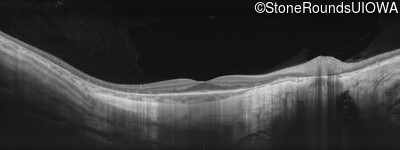

Age at visit: 36 years

This 30 year old man has had some difficulty seeing in dim light for the past few years.